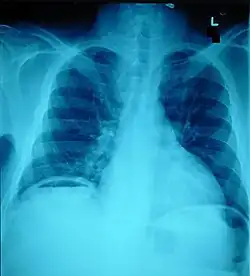

The small intestine takes up a large part of the abdomen and is likely to be damaged in penetrating injury.[5] The bowel may be perforated.[4] Gas within the abdominal cavity seen on CT is understood to be a diagnostic sign of bowel perforation; however intra-abdominal air can also be caused by pneumothorax (air in the pleural cavity outside the lungs that has escaped from the respiratory system) or pneumomediastinum (air in the mediastinum, the center of the chest cavity).[4] The injury may not be detected on CT.[4] Bowel injury may be associated with complications such as infection, abscess, bowel obstruction, and the formation of a fistula.[4] Bowel perforation requires surgery.[4]

Ten percent of people with polytrauma who had no signs of abdominal injury did have evidence of such injuries using radiological imaging.[1] Diagnostic techniques used include CT scanning, ultrasound,[1] and X-ray.[7] X-ray can help determine the path of a penetrating object and locate any foreign matter left in the wound, but may not be helpful in blunt trauma.[7] Diagnostic laparoscopy or exploratory laparotomy may also be performed if other diagnostic methods do not yield conclusive results.[5]